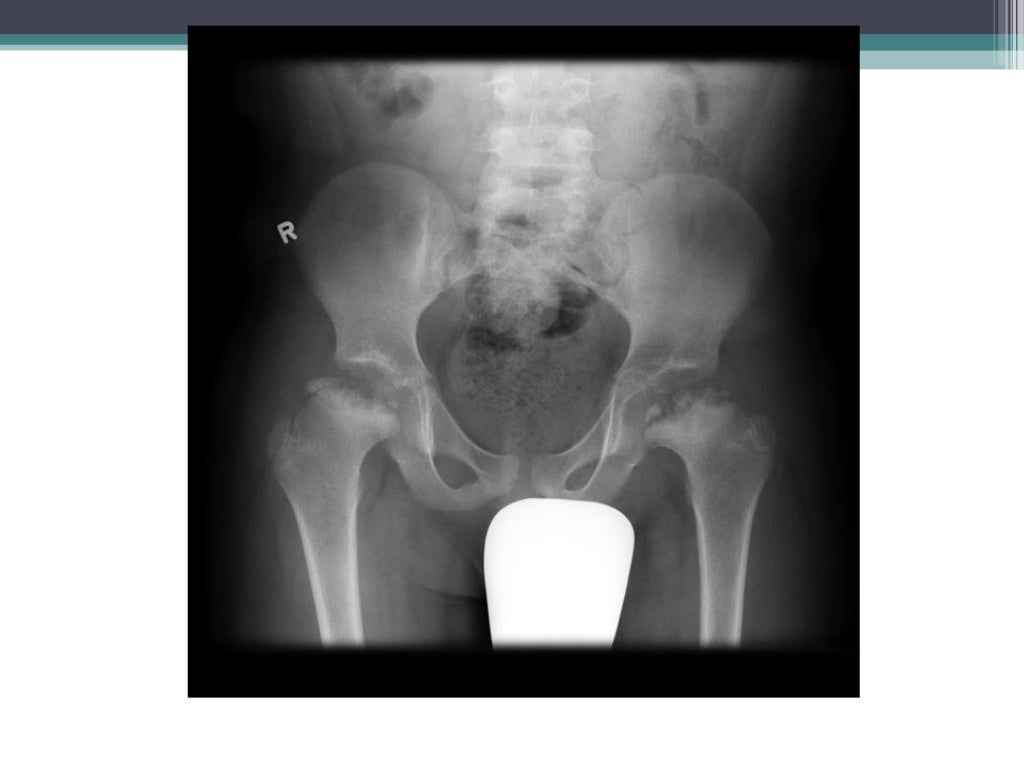

In dogs, it is most often seen in the miniature and toy breeds between the ages of 4 months to a year. The blood supply to the hip joint is interrupted and causes the bone cells to die, in a process called avascular necrosis. Ap view of both hips show a right capital femoral epiphysis which is fragmented and collapsed (white arrow) while the joint space, as is characteristic at this stage, remains.